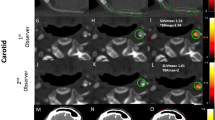

Sudden fibrous cap disruption of 'high-risk' atherosclerotic plaques can trigger the formation of an occlusive thrombus in coronary arteries, causing acute coronary syndromes. High-risk atherosclerotic plaques are characterized by their specific cellular and biological content (in particular, a high density of macrophages), rather than by their impact on the vessel lumen. Early identification of high-risk plaques may be useful for preventing ischemic events. One major hurdle in detecting high-risk atherosclerotic plaques in coronary arteries is the lack of an imaging modality that allows for the identification of atherosclerotic plaque composition with high spatial and temporal resolutions. Here we show that macrophages in atherosclerotic plaques of rabbits can be detected with a clinical X-ray computed tomography (CT) scanner after the intravenous injection of a contrast agent formed of iodinated nanoparticles dispersed with surfactant. This contrast agent may become an important adjunct to the clinical evaluation of coronary arteries with CT.